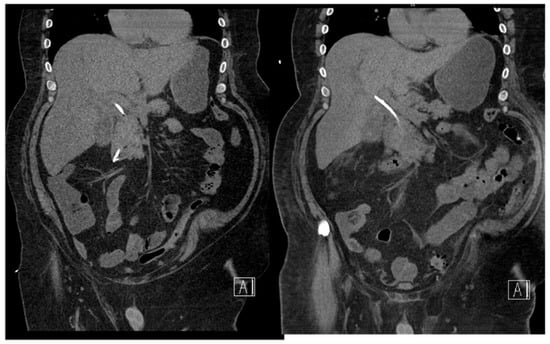

18.02: Contrast-enhanced CT demonstrated only mild hilar bile duct dilation, with no mass or lymphadenopathy (Figure 3).

Figure 3. CT scan (18.02.2025): discrete hilar duct dilation, no visible mass.

CT at readmission: No significant interval change, plastic stent in situ, no evidence of ductal dilation or masses (Figure 7).

Figure 7. CT scan (1.03.2025): no duct dilation, stent in situ, no new findings. A: anterior.